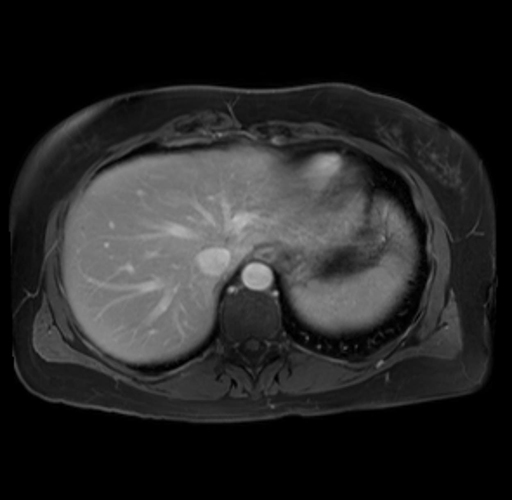

Imaging Analysis

Look through the patient's CT scan to identify any areas of concern for the necessary procedure.

Based on your CT findings, which issue(s) are present and would give reason for "planned slowing down moment(s)" in this case?